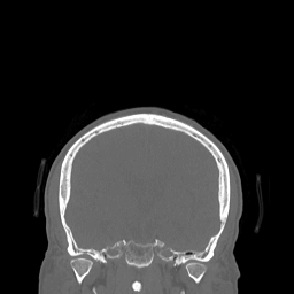

Model-based treatment planning for transcranial ultrasound therapy typically involves mapping the acoustic properties of the skull from an x-ray computed tomography (CT) image of the head. Here, three methods for generating pseudo-CT images from magnetic resonance (MR) images were compared as an alternative to CT. A convolutional neural network (U-Net) was trained on paired MR-CT images to generate pseudo-CT images from either T1-weighted or zero-echo time (ZTE) MR images (denoted tCT and zCT, respectively). A direct mapping from ZTE to pseudo-CT was also implemented (denoted cCT). When comparing the pseudo-CT and ground truth CT images for the test set, the mean absolute error was 133, 83, and 145 Hounsfield units (HU) across the whole head, and 398, 222, and 336 HU within the skull for the tCT, zCT, and cCT images, respectively. Ultrasound simulations were also performed using the generated pseudo-CT images and compared to simulations based on CT. An annular array transducer was used targeting the visual or motor cortex. The mean differences in the simulated focal pressure, focal position, and focal volume were 9.9%, 1.5 mm, and 15.1% for simulations based on the tCT images, 5.7%, 0.6 mm, and 5.7% for the zCT, and 6.7%, 0.9 mm, and 12.1% for the cCT. The improved results for images mapped from ZTE highlight the advantage of using imaging sequences which improve contrast of the skull bone. Overall, these results demonstrate that acoustic simulations based on MR images can give comparable accuracy to those based on CT.